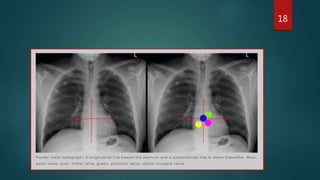

CXR

 chest x-ray are not performed on a routine basis in the absence of a specific

indication.

 It can be helpful in identification of valve type if information about valve is not

available.

17

CXR  chest x-rayare not performed on a routine basis in the absence of a specific indication.  It can be helpful in identification of valve type if information about valve is not available. 17